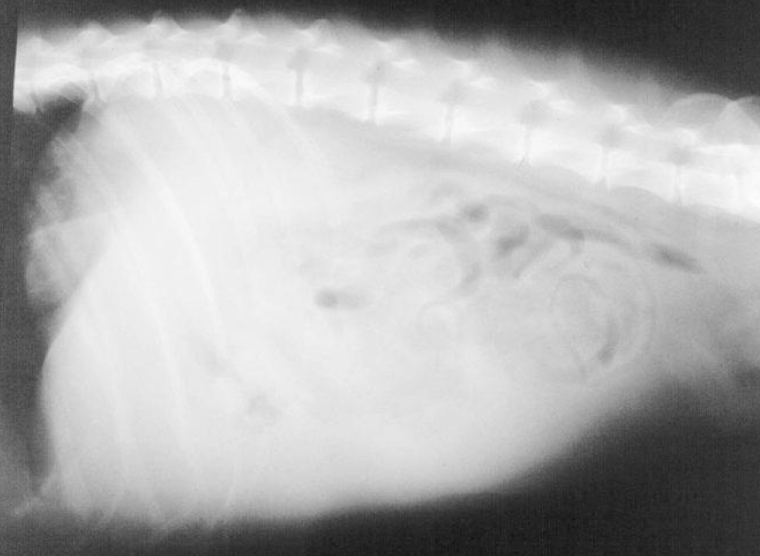

Describe this radiograph.

Loss of abdominal detail with focal or generalized “ground glass” appearance

What is the classic description of hemoabdomen rads?